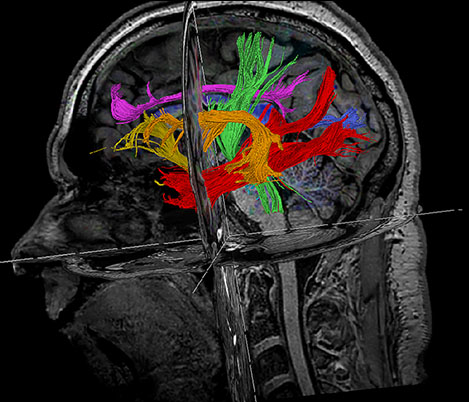

I believe that MRI provides us with a direction towards hypo fractionation, and potentially less toxicity. MR has already become deeply integration into our clinical practice. We have clinical protocols for planning the treatment of virtually all tumor sites like pelvis, brain and esophagus for external beam radiation therapy.

Prof. Dr. M. van Vulpen, Chairman Radiation Oncology Department, Radiation Oncologist, UMC Utrecht, The Netherlands

We’ve worked intensively with Philips for the past 10 years on new developments that make it easier to integrate MRI into our clinical practice. Like dedicated sequences for radiotherapy that give us the high contrast and high geometric fidelity we need for treatment planning.

Dr. C.A.T. van den Berg, MR Physicist, UMC Utrecht, The Netherlands